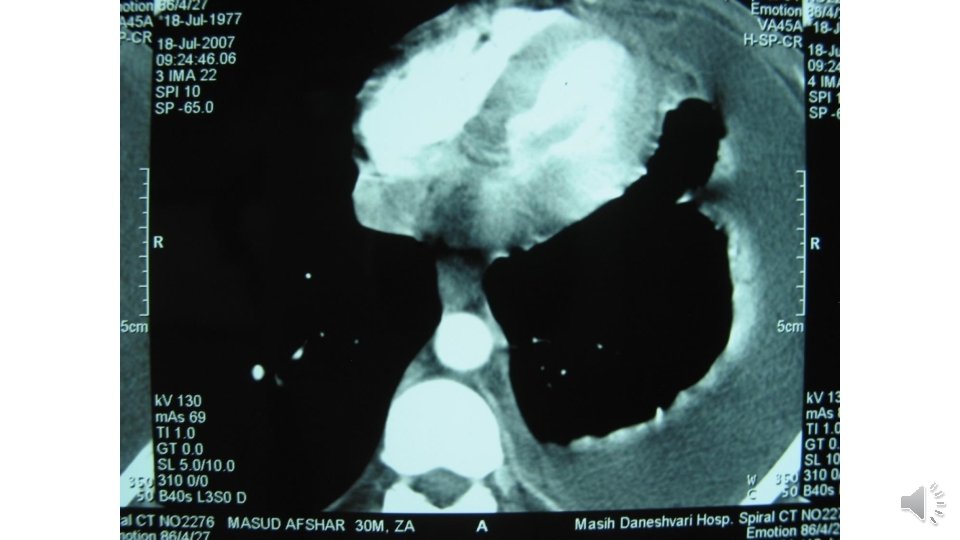

TB Spondylitis

Spread of TB spondylitis through the left psoas muscle to the left groin

Psoas abscess tracking down into the left inguinal region